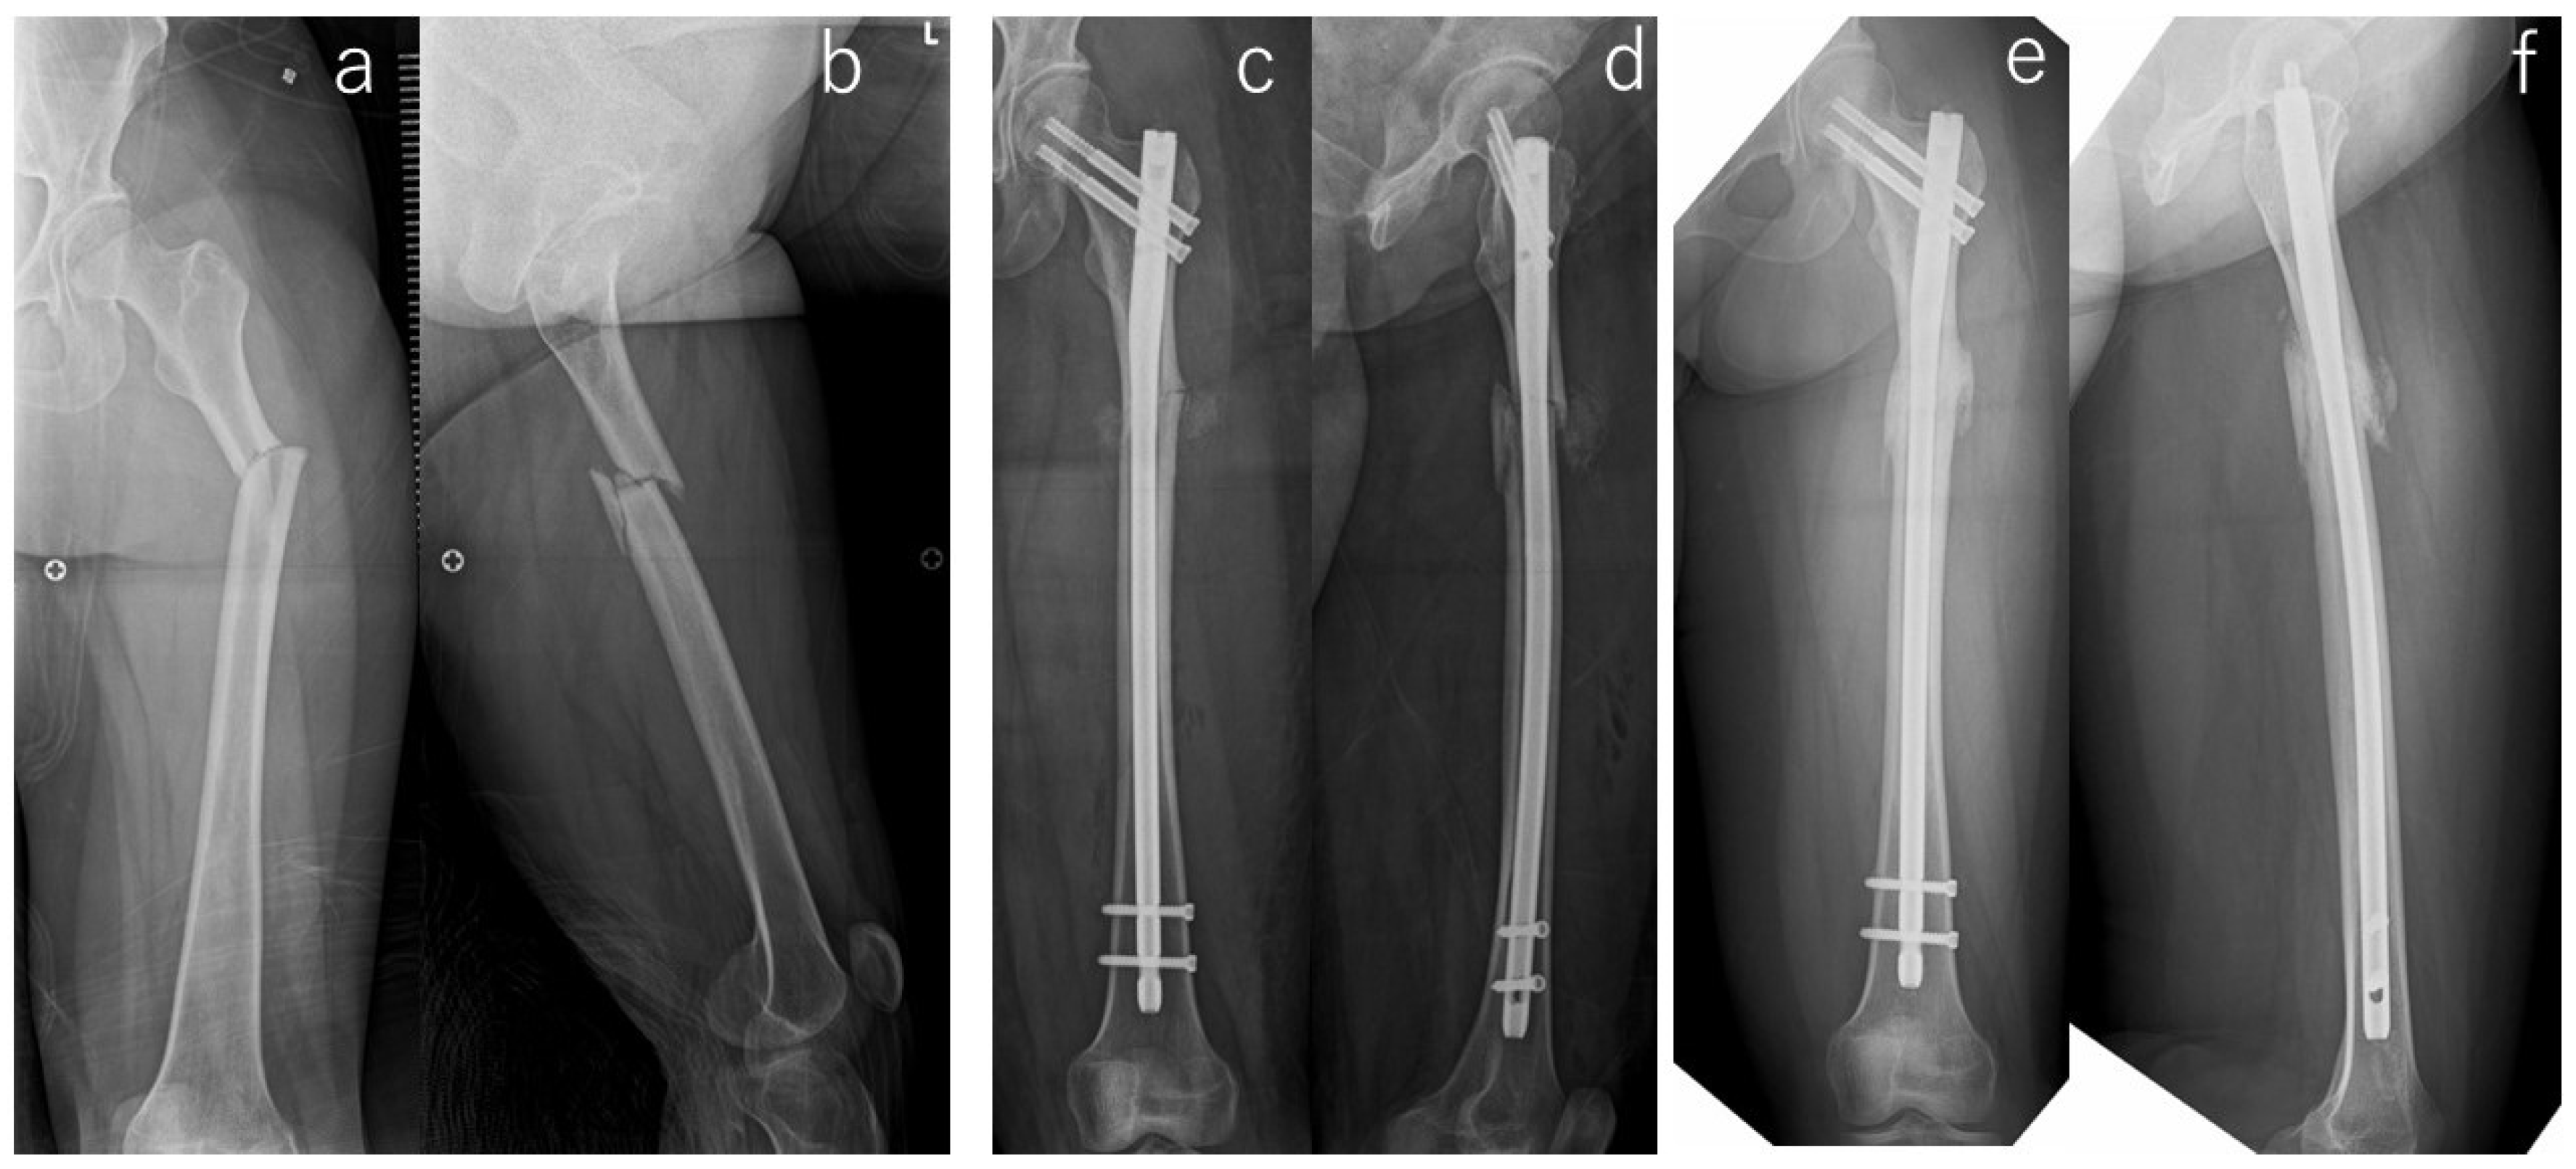

| Implant | Operative Procedure | Adjuvant Therapy | Malalignment | Cortical Discontinuity (-/Direction) | Fracture Gap | Correction Loss | Duration of Bone Union/Nonunion | ||||||

|---|---|---|---|---|---|---|---|---|---|---|---|---|---|

| Open Reduction | Bone Graft | Drilling | LIPUS # | Teriparatide | AP View | Lateral View | AP View | Lateral View | AP View | Lateral View | |||

| Antegrade intramedullary nail | - | - | - | - | - | - | - | - | Posterior | + | - | - | 6 months |

| Antegrade intramedullary nail | - | - | - | - | - | - | - | - | Posterior | + | - | - | 10 months |

| Cephalomedullary long nail | - | - | - | - | - | Varus | - | - | Posterior | - | - | - | Non-union (atrophic) * |

| Cephalomedullary long nail | - | - | - | - | - | - | - | - | Posterior | - | - | - | 16 months |

| Antegrade intramedullary nail | - | - | - | + | - | - | - | - | - | - | - | - | 18 months |

| Antegrade intramedullary nail | - | - | - | + | - | - | - | - | Posterior | - | + | + | Non-union (Hyper) * |

| Antegrade intramedullary nail | + | - | + | + | + | - | - | - | Posterior | + | - | - | Non-union (atrophic) |

| Cephalomedullary long nail | - | - | - | + | + | - | - | - | Posterior | + | - | - | 36 months |

| Antegrade intramedullary nail | - | - | - | + | + | - | - | - | Posterior | + | - | - | 10 months |

| Cephalomedullary long nail | + | + | + | + | - | - | - | - | - | + | - | - | Non-union (atrophic) * |

| Cephalomedullary long nail | - | - | - | + | + | - | Extension | - | Posterior | + | - | - | 21 months |

| Cephalomedullary long nail | - | + | + | + | + | Varus | - | - | - | - | - | - | 6 months |

| Cephalomedullary long nail | + | - | - | + | + | - | - | - | - | + | + | - | Non-union (atrophic) * |

| Antegrade intramedullary nail | + | - | - | + | + | - | - | - | - | - | - | - | 20 months |

| Cephalomedullary long nail | + | - | + | + | + | - | Extension | - | Posterior | + | - | - | Non-union (atrophic) * |

| Cephalomedullary long nail | - | - | - | + | + | - | - | - | - | - | - | - | 6 months |

| Antegrade intramedullary nail | - | - | - | + | + | - | - | - | - | + | - | - | 9 months |

| Antegrade intramedullary nail | + | - | + | + | + | - | - | - | - | - | - | - | Non-union (atrophic) |

| Antegrade intramedullary nail | - | - | - | + | - | Varus | - | - | Posterior | - | - | - | 5 months |

| Antegrade intramedullary nail | - | - | - | + | + | Varus | - | - | - | + | - | - | 8 months |